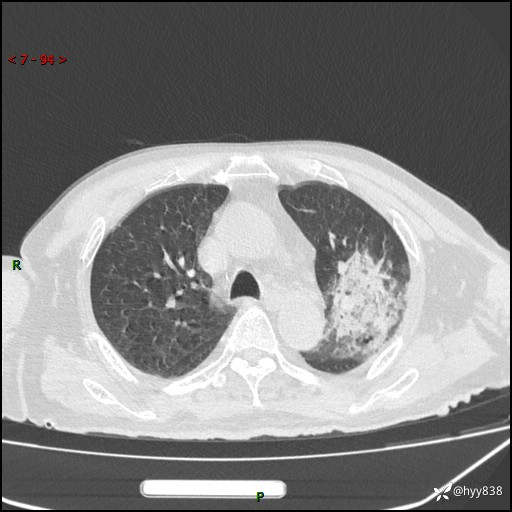

胸部CT复查(2024.8.5)